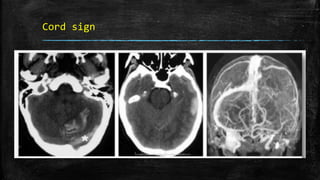

Cord sign

• #69 g